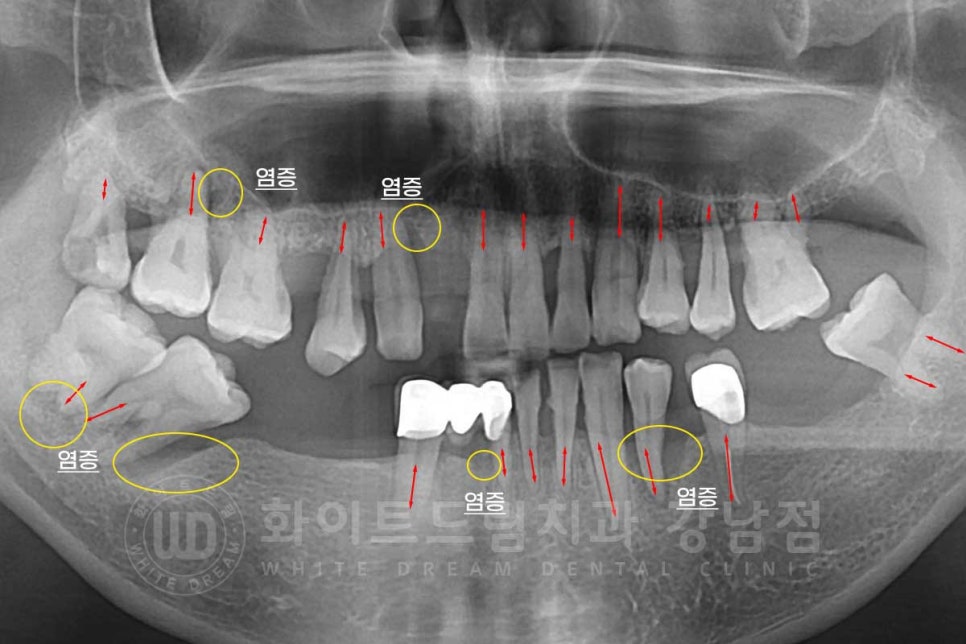

초진 x-ray 사진을 보면 많은 치아들이 있는 상태이지만

치아를 잡고 있는 잇몸뼈 면적이 적은 것이 확인됩니다.

정상적인 상태는 잇몸뼈가 치아의 2/3 정도를 덮고 있는 상태인데

환자분은 치주염으로 골 흡수가 많이 진행되어 있어

대부분의 치아가 흔들리고 있는 상태였습니다.